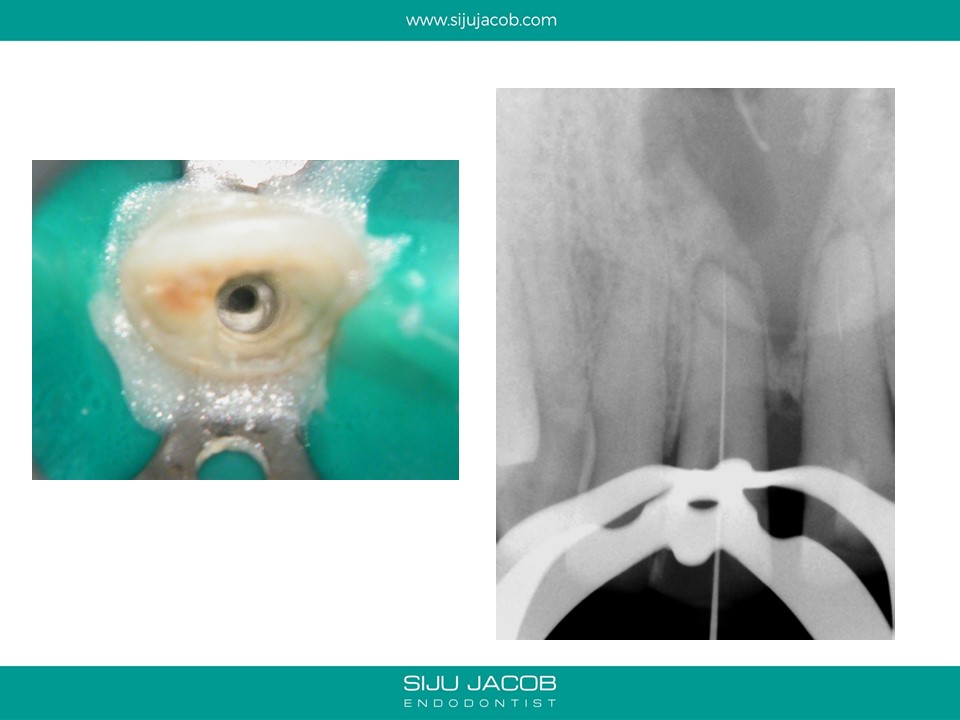

This was a case which was started by another clinican. A Naso-palatine cyst was mis-diagnosed as lesion of endodontic origin. The clinician opened up two central incisors, broke an instrument in one, couldn’t locate the canal (nearly perforated) and then referred the case.